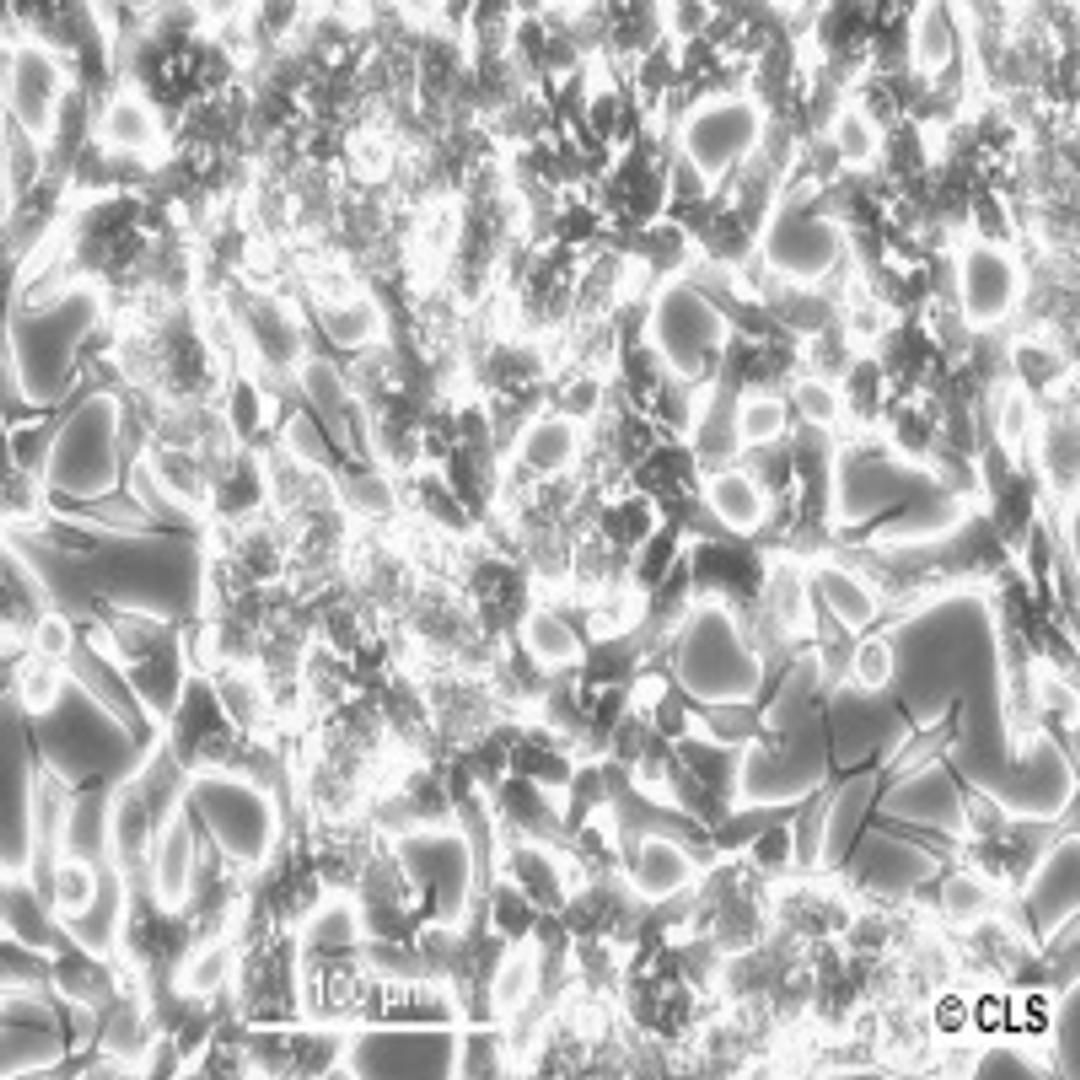

Human Prostate Adenocarcinoma cell line LNCaP

Morphology: Epithelial

Growth Properties: Clusters; lightly adherent

Description: This cell line was established from a metastatic lesion of human prostatic adenocarcinoma.